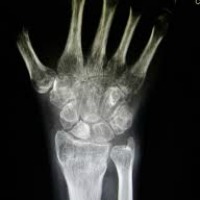

È una radiografia al polso a determinare il destino dei giovani migranti

radiografiaIl destino dei migranti non accompagnati che approdano sulle coste italiane passa per una radiografia al polso sinistro. Si tratta di una tecnica basata sul presupposto che sia possibile definire l’età di una persona dal grado di calcificazione delle sue ossa. Viene utilizzata, al pari di altre procedure come l’analisi dello sviluppo puberale e dell’apparato dentario, per stabilire se i giovani immigrati privi di documenti abbiano più o meno di 18 anni. Il che è fondamentale per il loro futuro. Se risultano minorenni vengono avviati a un progetto di integrazione sociale, potranno studiare l’italiano ed essere avviati all’apprendimento di un mestiere. Se viceversa si rivelano maggiorenni, ciò che li aspetta è il trasferimento in un Centro di identificazione ed espulsione e quindi il rimpatrio forzato.

Questo prevede la legge italiana, che però non tiene conto di 2 fattori determinanti. Il primo: nel nostro Paese non esiste un criterio unico e ogni struttura di accoglienza usa il suo metodo. Il secondo: è scientificamente accertato che la radiografia del polso offre risultati estremamente incerti, perché lo sviluppo delle ossa è condizionato da molti fattori, dall’alimentazione a eventuali malattie. Basti pensare che anche 2 fratelli possono avere uno sviluppo scheletrico differente per capire quanto approssimativo possa essere il responso di tale metodo in relazione a ragazzi provenienti da etnie e zone del mondo diverse.

“Una possibile soluzione – afferma Salvatore Fachile, avvocato dell’Associazione per gli studi giuridici sull’immigrazione – è un approccio multidisciplinare. L’età va stabilita mettendo assieme più strumenti di indagine. Si tratta della procedura prevista dal ‘protocollo di Ascone’, sviluppato dal Ministero della Salute e avallato dal Consiglio superiore della sanità, ma non ancora adottato dal Ministero dell’Interno”. Il procollo di Ascone, dal nome del medico e dirigente ministeriale considerato il padre del documento, pur non negando la rilevanza della radiografia al polso, considerato il suo margine di errore stimato in 2 anni, la inserisce nell’ambito di una valutazione più ampia che prevede l’esame fisico del ragazzo e della sua maturazione sessuale, l’individuazione di eventuali disturbi dello sviluppo e lo stato della dentizione.